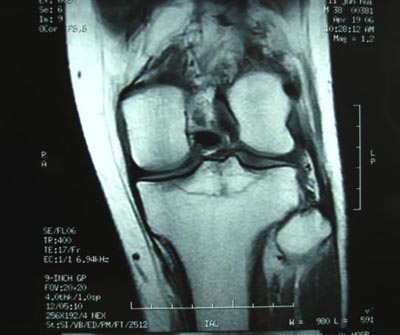

男,45。骑摩托车摔伤左膝肿痛三天,浮髌(+),活动受限。请大家看看片子有问题吗?

标题: 现将mri结果公布

手术证实是后交叉韧带胫骨附着处撕脱骨折。

术中用可吸收螺钉固定。